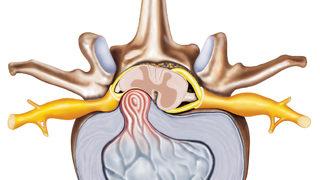

Bel fıtığı, günümüzde birçok insanın karşılaştığı yaygın bir sağlık sorunu olarak dikkat çekiyor. Bu sayfada, bel fıtığı haberleri ile birlikte, hastalığın sebepleri, tedavi yöntemleri ve en son gelişmeleri bulabilirsiniz. Yazılarımızda, son dakika bel fıtığı haberi ve güncel bel fıtığı haberleri gibi benzersiz içerikler sunarak okuyucularımızı bilgilendirmeyi amaçlıyoruz. Ayrıca, bu konuda uzman görüşlerine de yer vererek, tedavi süreçlerini ve iyileşme yollarını aktarma fırsatını bulacaksınız.

Son dönemde artan bel fıtığı vakaları ve bu konudaki tıbbi yenilikler, bu sorunla mücadelede önemli adımlar atılmasına neden oldu. Sayfamızdan, bel fıtığı ile ilgili en son gelişmelere ulaşabilir, sağlığınızı etkileyebilecek kritik bilgileri edinebilirsiniz. Güncel bel fıtığı haberleri ile her zaman dikkat çekecek bu alandaki yeniliklerden haberdar olmanız için sürekli güncellenen içeriklerimizi takip edin.